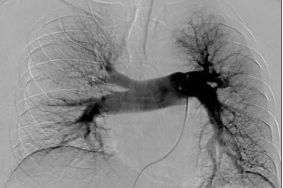

左侧下肢肿胀半月伴急性呼吸困难3天,CT和DSA造影检查发现肺内可见大块血栓,诊断为肺栓塞。

经植入下腔静脉滤器,肺动脉置管溶栓后,肺动脉内血栓消失。

再行左侧髂静脉造影,发现大量血栓形成。

治疗前

置管接触性溶栓后,血栓消失,下肢肿胀消失。

治疗后